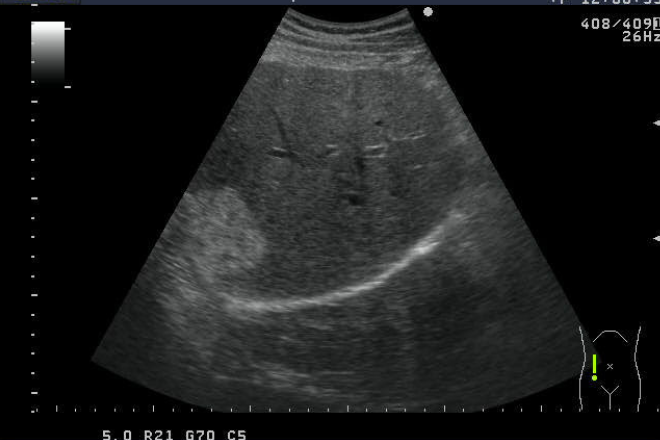

El hígado tiene 8 segmentos, cada uno con ramas de la arteria hepática, vena porta, vena hepática, linfáticos y drenaje biliar.

Tiene 4 secciones básicas, producidas por las venas hepáticas derecha, media e izquierda.

El lóbulo izquierdo contiene los segmentos 2, 3, 4A y 4B, mientras que el derecho contiene los segmentos 5, 6, 7 y 8.

El hígado recibe suministro sanguíneo de la vena porta y la arteria hepática.

Las venas hepáticas, derecha, media e izquierda, recogen sangre del hígado y se dirigen a la VCI debajo del diafragma.